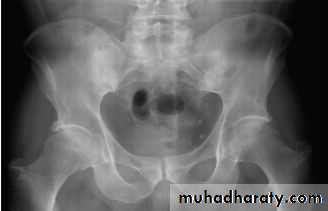

X-rays of the sacroiliac joint show irregularity and loss of cortical margins, widening of the joint space and subsequently sclerosis, joint space narrowing and fusion.Lateral thoracolumbar spine X-rays may show anterior ‘squaring’ of vertebrae due to erosion and sclerosis of the anterior corners and periostitis of the waist.

Erosive changes may be seen in the symphysis pubis, ischial tuberosities and peripheral joints.